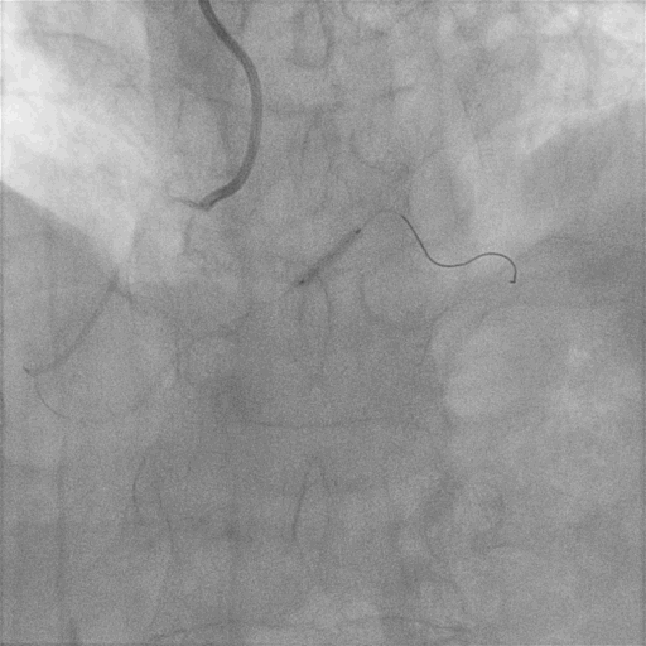

左图:LM未见狭窄及阻塞病变;

右图:LCX未见狭窄及阻塞病变;

左图:LAD近段可见斑块,中段原支架通畅,未见狭窄及阻塞病变;

右图:RCA开口狭窄约50%,近段中段弥漫性斑块,远段后侧支第二转折处局限性狭窄90%;

患者不稳定型心绞痛症状典型,根据心电图及冠状动脉造影术结果回报,考虑罪犯血管为右冠脉远段后侧支第二转折处病变;

右冠状动脉全程迂曲伴钙化,可能会为随后器械推送带来阻力和困难;